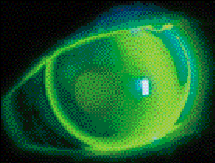

Slit lamp evaluation with both cobalt blue illumination and a Wratten or Tiffen filter will dictate the amount of change in base curve radius that's required. A slight apical clearance fitting relationship will often be present. The base curve can then be changed in 0.50D to 1.00D steps until apical bearing is first observed. At this time, a "three-point touch" or "bull's eye" fitting relationship should be present (Fig. 1).

FIG. 1: A "three-point touch" fitting relationship in a

keratoconic cornea.